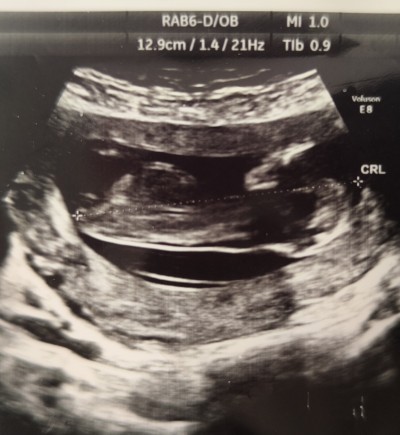

Dr emin olamadi cinsiyet konusunda fikirlerinizi alabilir miyim 13+1 haftalık

Gebelik haftası 13+1